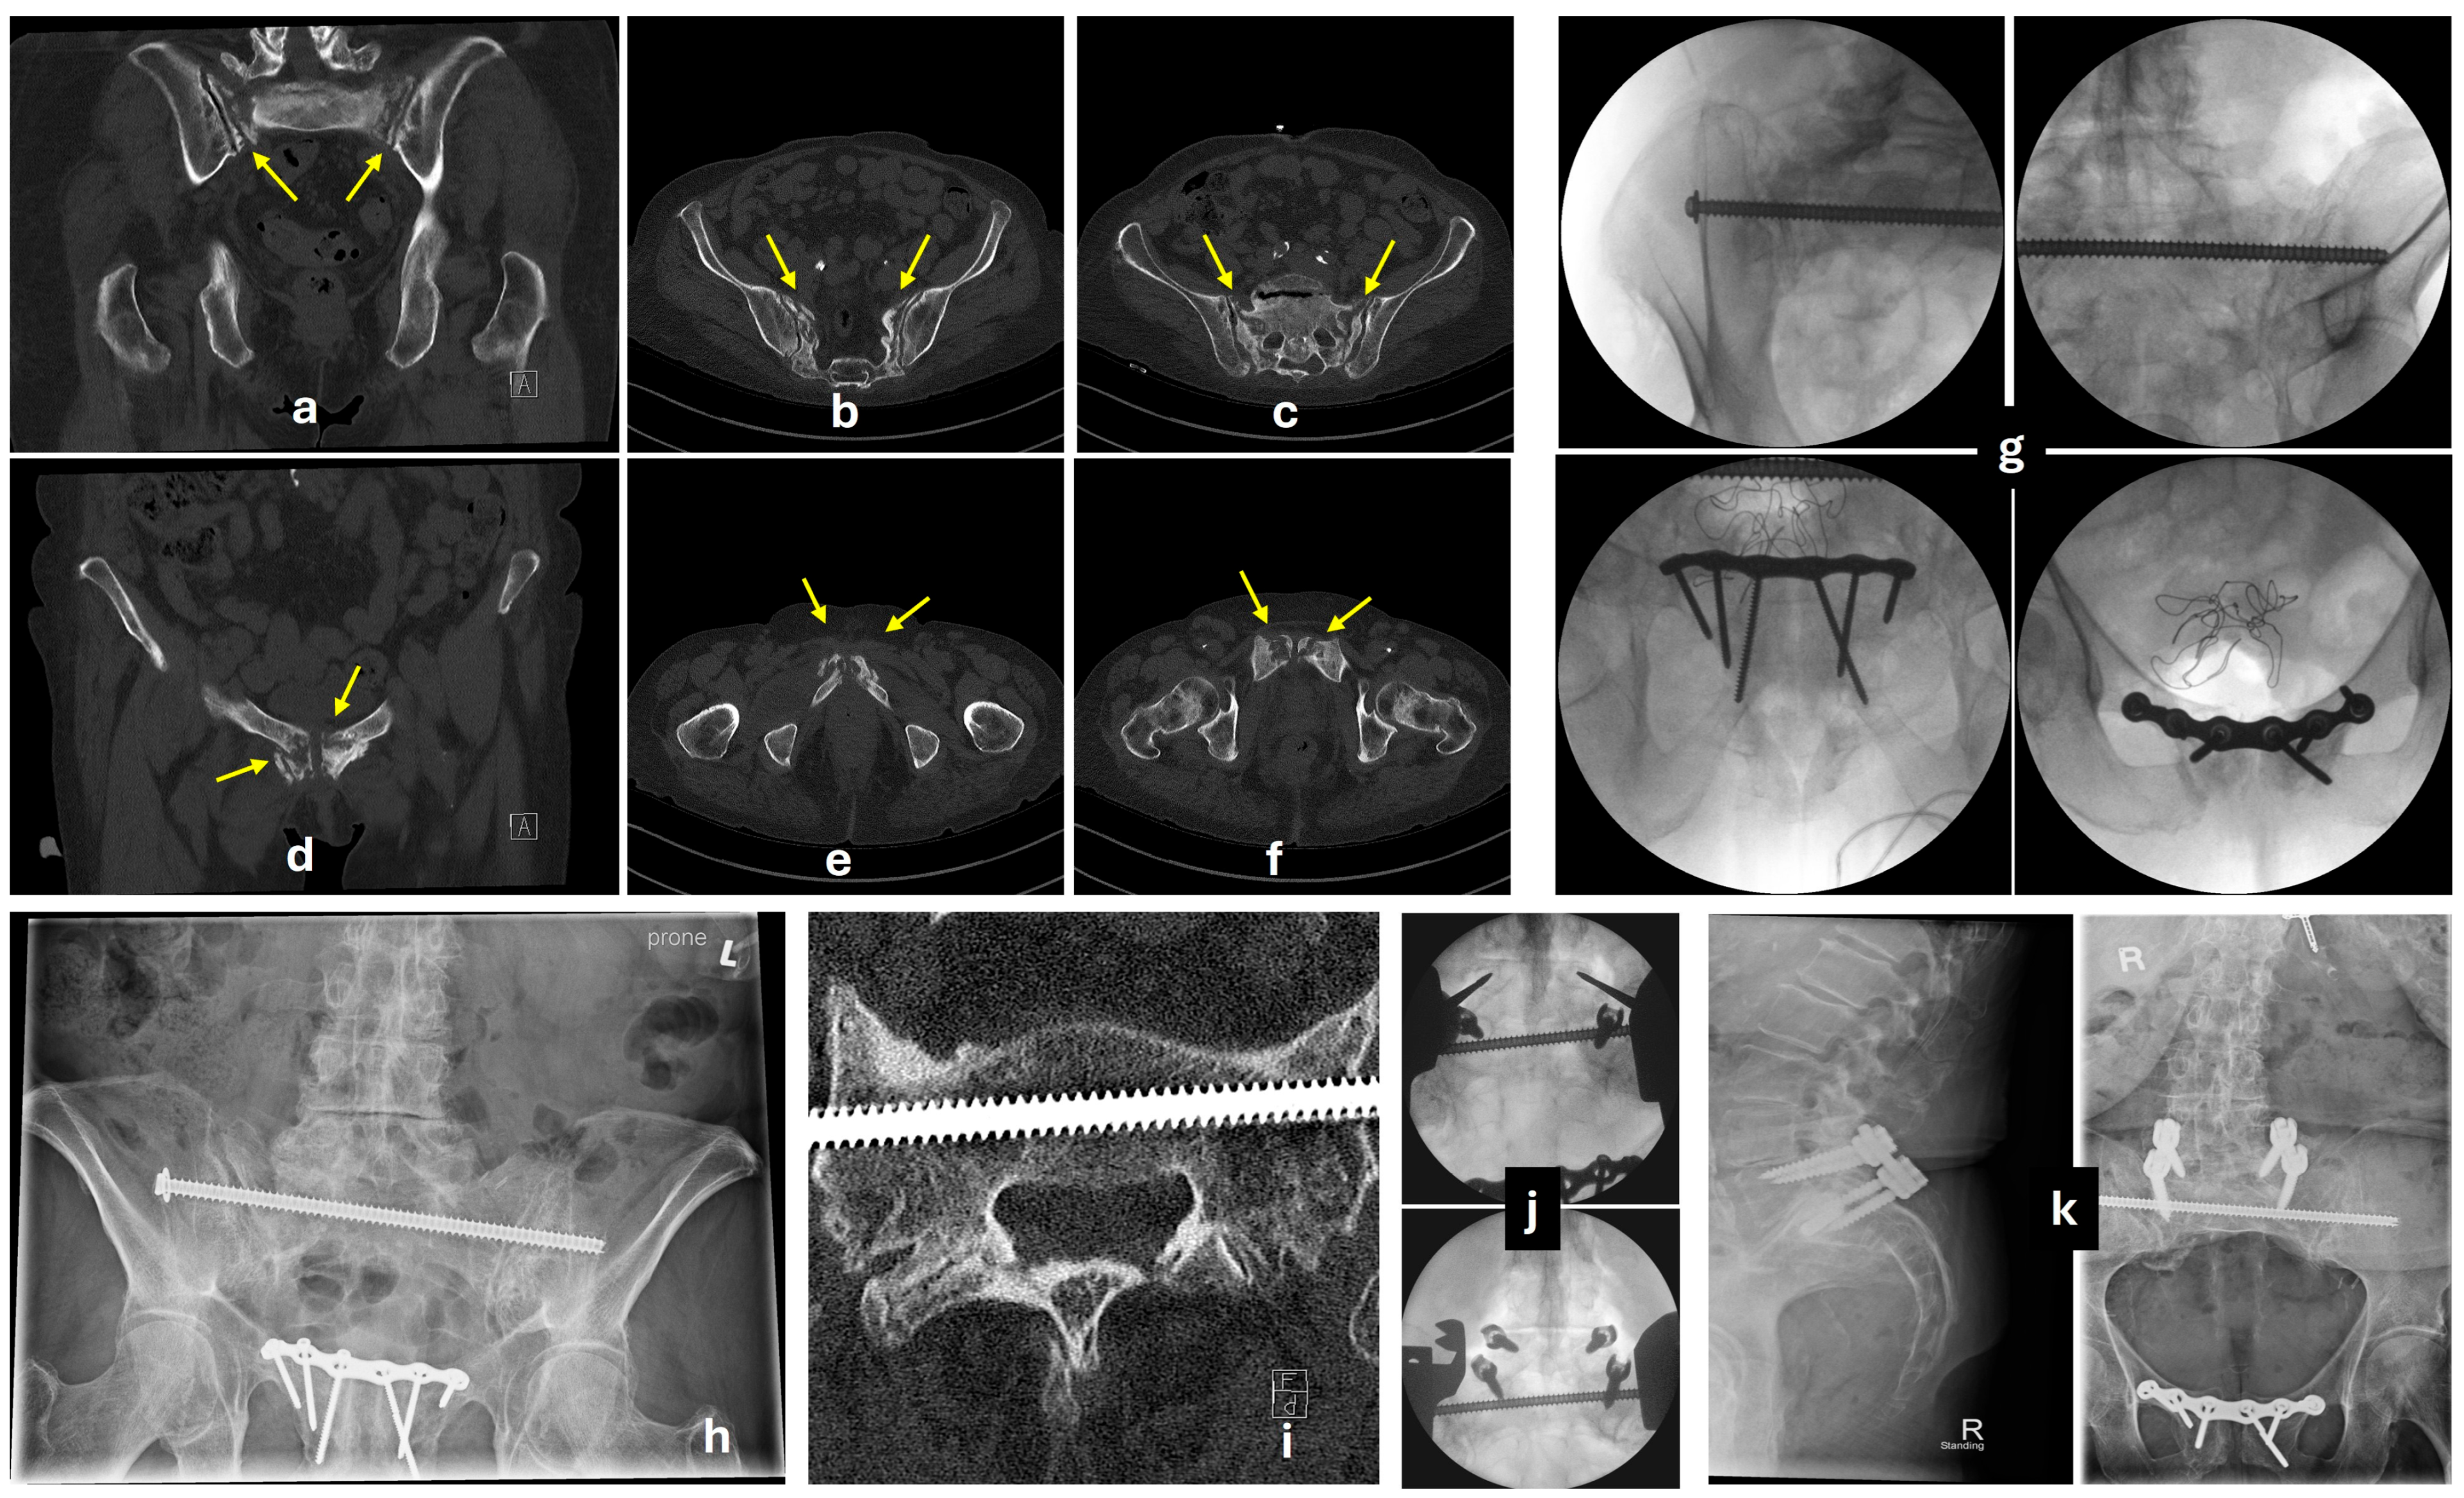

5.3. Posterior Fixation

5.3.1. Transiliac-Transsacral Screws

5.3.2. Transiliac Bridge Plating

5.3.3. Lumbopelvic Fixation

5.4. Anterior Fixation

5.4.1. Conventional Anterior Plating

5.4.2. Percutaneous Screw Fixation

5.4.3. External Fixator